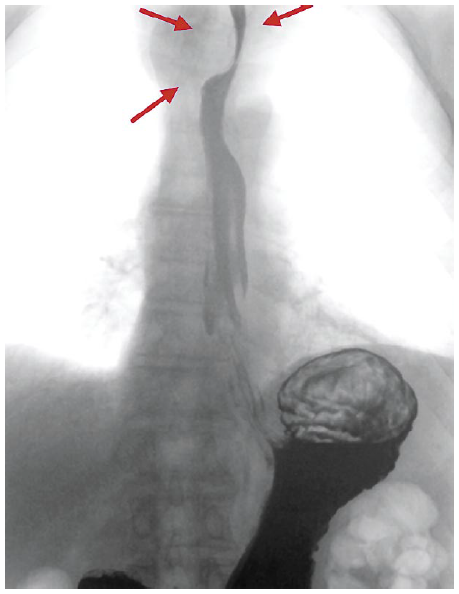

Пациент И., 72 г. Из анамнеза известно, что с 1999 г. выявлена язвенная болезнь ДПК. Проводилась консервативная терапия с положительной динамикой без последующего наблюдения. Клинические симптомы обострения отмечал давно. В 2014 г. появились жалобы на периодическую изжогу. Самостоятельно принимал антисекреторные препараты с клинически положительным эффектом, с последующей самостоятельной отменой. С марта 2017 г. жалобы на изжогу приобрели постоянный характер, в связи с чем проведена эзофагогастродуоденофиброскопия (ЭФГДС). Выявлена язва пищевода, рубцовая деформация луковицы ДПК. С марта по декабрь 2017 г. проведена терапия ингибиторами протонной помпы, антацидами без выраженного положительного эффекта, после чего пациент вновь пропал из поля зрения специалистов. В январе 2018 г. появились периодические жалобы на затруднение при глотании твердой пищи, чувство кома в горле. При повторной ЭФГДС выявлены хронические язвы нижней трети пищевода до 4 см, эрозивный дуоденит, рубцовая деформация луковицы ДПК. По данным биопсии – картина полной тонкокишечной метаплазии. Helicobacter pylori (-). Далее пациенту выполнена рентгенография желудочно-кишечного тракта с барием. Выявлено образование до 5 см в средостении, сдавливающее пищевод. Рубцовая деформация пищевода, подозрение на язву пищевода. Скользящая кардиофундальная грыжа пищеводного отверстия диафрагмы. Гастроптоз. Рубцовая деформация луковицы ДПК. Гипертонус ДПК (рис. 1). От предложенного выполнения мультиспиральной компьютерной томографии (КТ) на тот момент отказался.

Рис. 1. Результат рентгеноскопии желудочно-кишечного тракта с бариевой взвесью.

Fig. 1. The result of gastrointestinal x-rays using barium suspension.